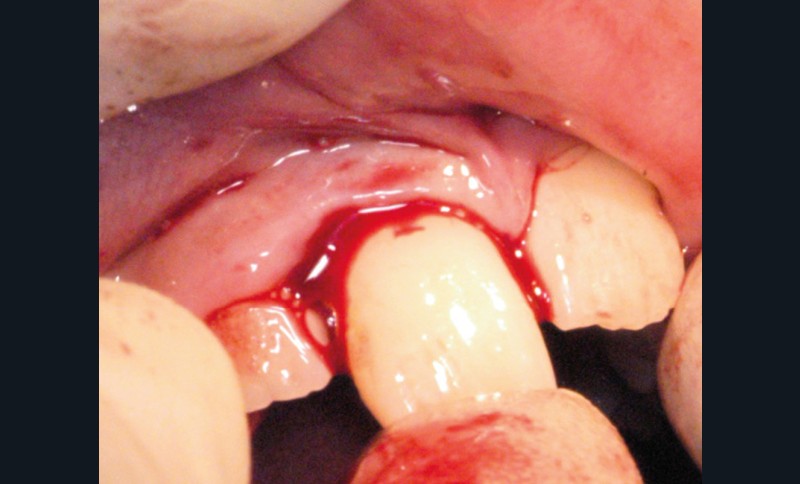

Enfant de 9 ans dont une incisive centrale maxillaire a été expulsée en jouant au football. Appel immédiat de la mère à qui l’on conseille de conserver la dent expulsée dans du sérum physiologique (fig. 1). Le temps extra-alvéolaire à sec a été inférieur à 5 minutes. Le patient arrive 40 minutes après le traumatisme dans l’Unité d’Odontologie pédiatrique. Après interrogatoire, examen clinique et radiographique, un rinçage de l’alvéole est effectué et la dent est réimplantée le plus rapidement possible (fig. 2). Une contention semi-rigide est ensuite placée (fig. 2). La dent étant mature, la prise en charge endodontique (séance de Ca(OH)2 puis obturation à la gutta percha) débute deux semaines plus tard (fig. 3 et 4) afin de limiter les risques d’infection, de résorption. Le suivi sur quatre années montre une dent fonctionnelle, sans ankylose ni résorption radiculaire ou osseuse.